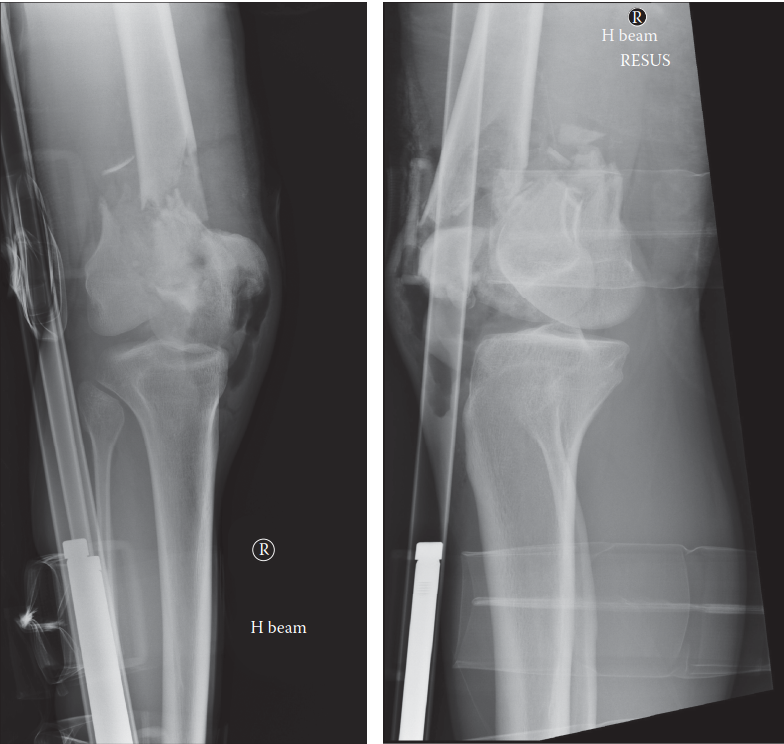

تُعد كسور عظم الفخذ السفلية (Distal Femoral Fractures) من الإصابات المعقدة التي تُصيب الجزء السفلي من عظم الفخذ، وتحديداً في منطقة تبعد حوالي 9 سنتيمترات عن خط مفصل الركبة. تُعرف هذه المنطقة باسم المنطقة فوق اللقمية أو داخل اللقمية، وهي حيوية لحركة الركبة واستقرارها. هذه الكسور ليست مجرد كسر بسيط في العظم؛ بل هي تحدٍ كبير لجراحي العظام والمرضى على حد سواء، نظراً لقربها من مفصل الركبة الحساس وأهمية هذا المفصل في الحركة اليومية.

إن أهمية هذه الكسور تكمن في قربها من مفصل الركبة، مما يجعل استعادة الشكل التشريحي الدقيق للمفصل أمراً حاسماً. أي عدم تطابق في سطح المفصل بعد الكسر قد يؤدي إلى مضاعفات طويلة الأمد مثل التهاب المفاصل ما بعد الصدمة (خشونة الركبة) وتيبس المفصل، مما يُعيق قدرة المريض على المشي وأداء الأنشطة اليومية.

يُستخدم نظام تصنيف AO/OTA بشكل أساسي لتصنيف كسور عظم الفخذ السفلية، وهو يُساعد الجراحين على فهم طبيعة الكسر وتحديد خطة العلاج المناسبة:

النوع C:

كسر كامل داخل المفصل (يُصيب كلتا اللقمتين والجزء القريب من المفصل).

يُشير هذا التصنيف إلى مدى تعقيد الكسر والحاجة إلى دقة أكبر في الاستعادة التشريحية كلما زاد التورط المفصلي.

يمر الشريان والوريد المأبضي عبر الحفرة المأبضية، خلف الجزء السفلي من عظم الفخذ مباشرةً. كما يقع العصب الظنبوبي والعصب الشظوي المشترك على مقربة شديدة. تُشكل كسور عظم الفخذ السفلية عالية الطاقة، خاصةً تلك التي تُصاحبها إزاحة كبيرة أو ميلان خلفي، خطراً كبيراً لإصابة الأوعية الدموية والأعصاب (مثل تمزق الشريان المأبضي أو العصب الشظوي المشترك). لذا، فإن التقييم العصبي الوعائي الشامل قبل وأثناء الجراحة إلزامي.

التشخيص الدقيق لكسور عظم الفخذ السفلية

وسائل التصوير التشخيصي

الأشعة السينية (X-rays):

- هي الفحص الأول والأساسي لتشخيص كسور عظم الفخذ السفلية.

- يتم أخذ صور من الأمام والخلف (AP) ومن الجانب (Lateral) للركبة وعظم الفخذ بالكامل (بما في ذلك مفصل الورك والكاحل) لتقييم المحور الميكانيكي للطرف.

- يمكن أن تُظهر الأشعة السينية وجود الكسر، نوعه (فوق اللقمة، داخل اللقمة)، مدى الإزاحة، ودرجة التفتت.

- قد تُستخدم أشعة الشد (Traction radiographs) لتقييم قابلية الكسر للرد.

التصوير المقطعي المحوسب (CT Scan):

- يُعد ضرورياً لجميع كسور المفصل (النوع B و C حسب تصنيف AO/OTA) والكسور خارج المفصل شديدة التفتت.

- يُوفر صوراً ثلاثية الأبعاد (3D reconstructions) تُظهر تفاصيل دقيقة عن حجم الشظايا، مدى الإزاحة، أي تدرج في السطح المفصلي، وأي انحشار عظمي.

- هذه المعلومات حاسمة للأستاذ الدكتور محمد هطيف لوضع خطة جراحية دقيقة، خاصةً لكسور المفصل التي تتطلب استعادة تشريحية مثالية.

خيارات العلاج لكسور عظم الفخذ السفلية

العلاج الجراحي (التدخل الجراحي)

يُعد التدخل الجراحي المعيار الذهبي لمعظم كسور عظم الفخذ السفلية المزاحة. الأهداف الرئيسية هي: